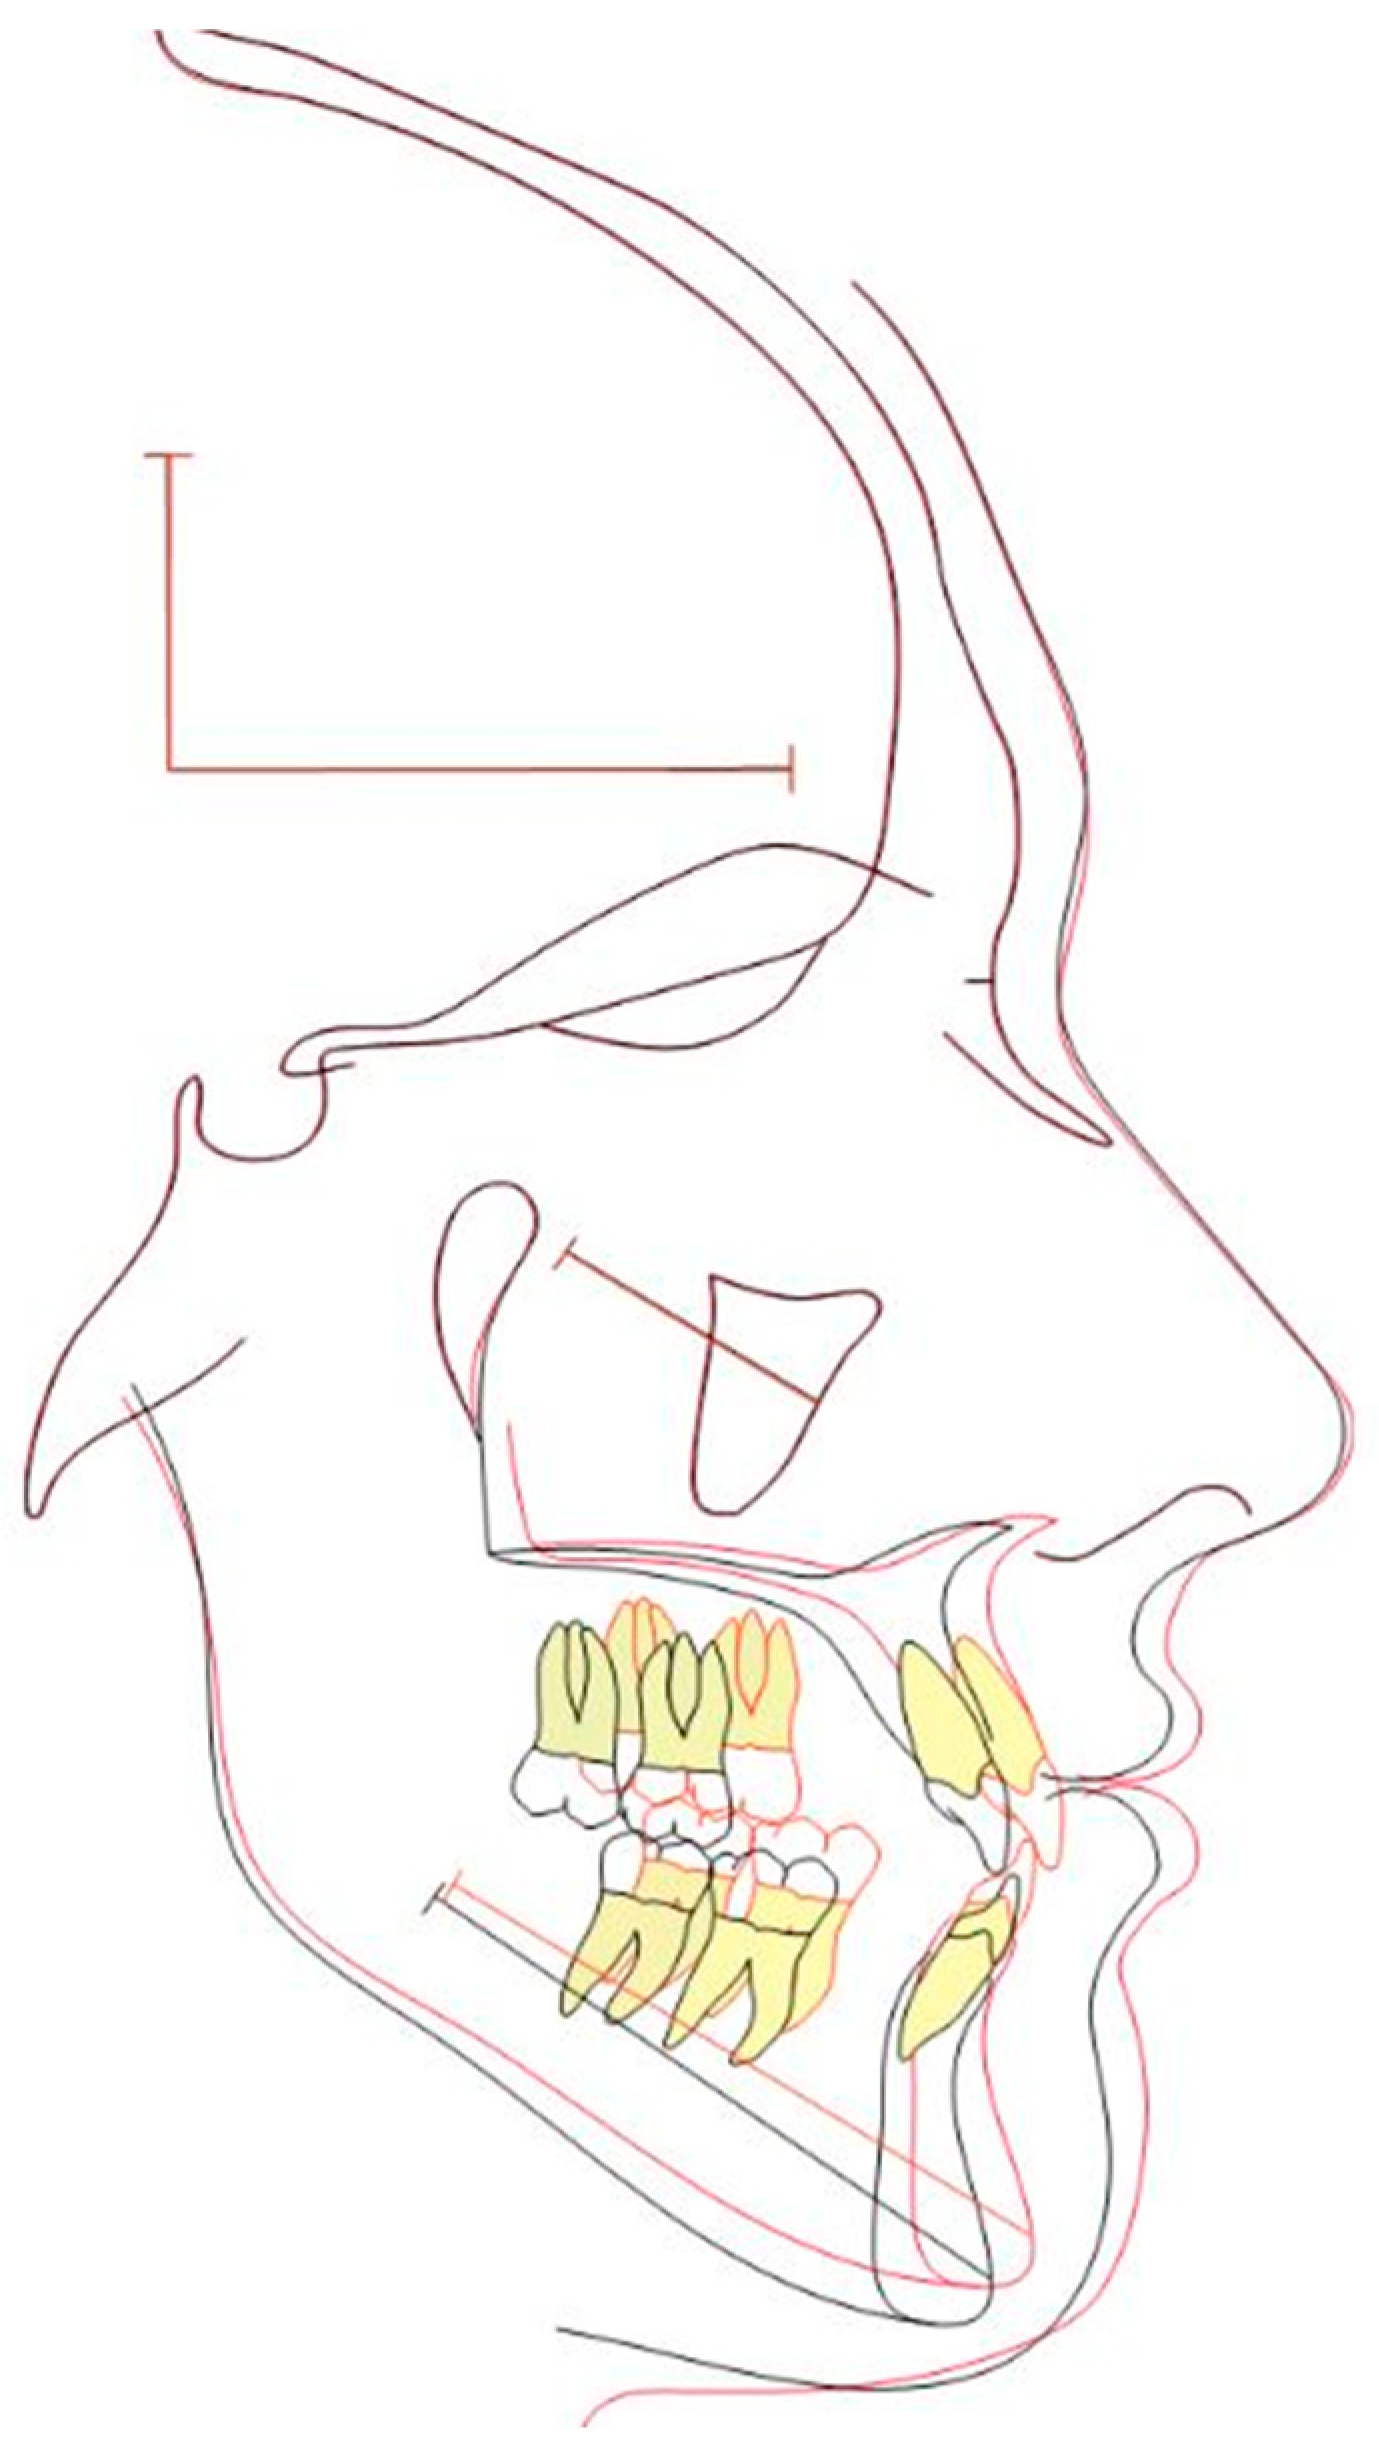

2.1. Diagnosis and Individual Treatment Planning